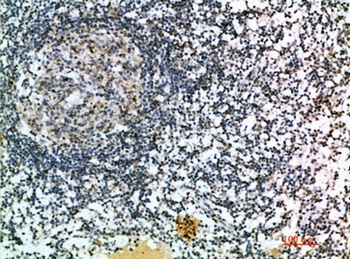

应用稀释比例:IHC-p 1:50-200, ELISA 1:10000-20000